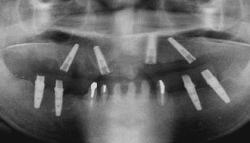

| 下顎の前歯部以外の全ての歯にグラツキがあったため、上顎はAll-on-4、下顎の奥歯は通常のインプラントブリッジとしました。 | |